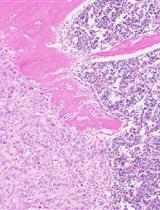

• The Ad-Cre-Luc-mediated ablation of Pten leads to hyperplasia that progresses through prostatic intraepithelial neoplasia (PIN) to adenocarcinoma.

Figure 4. Expression levels of PI3K/mTOR pathways' downstream components in mice's anterior prostate respond to Pten conditional knockout. This figure is adapted from the authors' published article, A Novel Controlled PTEN-Knockout Mouse Model for Prostate Cancer Study (Figure 2, Panels A–C). Frontiers in Molecular Biosciences [8]. (A) IHC staining to detect Cre recombinase in Pten LoxP/LoxP (L/L) mice's anterior prostate (AP) from different age groups that are infected with different adenovirus vectors. Ad-CMV-Luc, adenovirus vector that expresses luciferase using a cytomegalovirus (CMV) promoter. Green arrows indicate the basal cells. Green dash lines outline the stroma. Green triangles point toward stroma cells. Pten, phosphatase and tensin homolog deleted on chromosome 10. Ad-Cre-Luc, adenovirus vector that co-expresses luciferase and Cre recombinase (also using the CMV promoter). (B) IHC staining to detect Pten and downstream components of the PI3K/mTOR pathways in Pten L/L mice's AP that were infected with Ad-CMV-Luc and Ad-Cre-Luc viral vectors. Red arrows indicate Pten-, P-Akt-, P-S6-, or P-4E-BP1-positive cells. P-S6, phospho-S6 ribosomal protein. P-4E-BP1, phospho-eukaryotic translation initiation factor 4E-binding protein 1. (C) Serial IHC staining to detect Pten and downstream components of the PI3K/mTOR pathways in Pten L/L mice's AP at 0, 4, 8, and 16 weeks from the surgical delivery of the viral vectors. Red arrows indicate Pten-negative cells with activated P-S6 and P-4E-BP1.